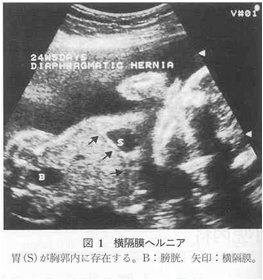

【产前诊断(Prenatal diagnosis)】

胎儿超声与MRI:可见胎儿胸腔内有腹部脏器